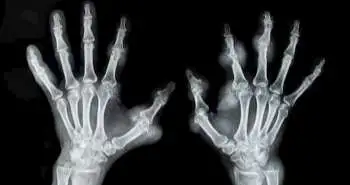

Attempts are proceeding to identify risk factors for rheumatoid arthritis (RA). Where smoking is an essential risk factor for RA, many individuals who never smoked also develop RA, this indicates the involvement of other factors such as diet and obesity as well. Other previous studies say that eating fish is a protective approach for rheumatoid arthritis (RA) risk possibly due to the anti-inflammatory influence of omega-3 fatty acid it contains, although this association has not been established explicitly. Therefore, this prospective cohort study was conducted with large sample size, repeated measures of dietary intake, and extended follow-up to assess the fish intake and RA risk by the age of onset, smoking and serologic status.

A total of 166,013 females from two prospective cohorts, the Nurses' Health Study (NHS) and NHSII were studied for evaluating the fish intake and RA risk association. Food frequency questionnaires were used to estimate the fish intake at baseline and every four years. A medical record review was utilized to assess incident RA during follow-up and serologic status. The estimated hazard ratios (HR) and 95% confidence intervals (CI) for fish intake frequency and RA was determined by applying Pooled Cox Regression. The analysis also investigated the smoking-fish synergy for RA risk.

One thousand eighty incident patients of RA were identified during the 3,863,909 person-years of follow-up. The enhanced intake of fish was not related to all RA or seronegative RA; however, had risen risk for RA diagnosed > 55 years old. The HRs of frequent fish intake (vs infrequent) for RA,  seronegative and seropositive RA among women ≤55 years old noticed to be was 0.73, 0.55, and 0.85, respectively. Smokers with frequent fish intake showed modest raised RA risk, and smokers with infrequent fish intake showed a highly elevated risk for RA onset ≤55 years. No clear protective impact of marine omega-3 fatty acid or fish intake was found on RA risk, overall or by serologic status, however, infrequent consumption of fish with smoking led to the elevated risk of RA.